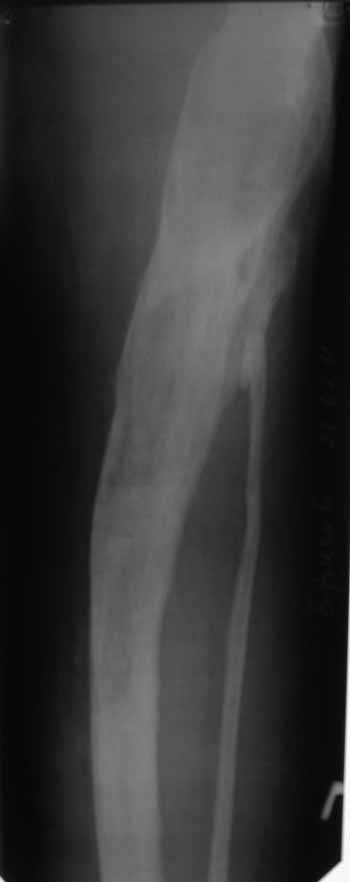

В анамнезе этапные операции по поводу устранения Coxa Vara, формирование артродеза коленного сустава, удлинения бедра. В данный момент беспокоит укорочение 7 см, эквинус стопы. Объективно: - местный статус виден на фото, сосудистых и неврологических расстройств нет. Обратился в консультативном порядке, настроен на удлинение голени в г.Волгограде. (со слов больного - не берут без санации очага на голени). Ваши предложения? Из кулуарных соображений - а не актиномикоз ли это? Иссечение рубцов+ VAC+ Стержень с аппаратом + микрососудистый трансплантат(?)